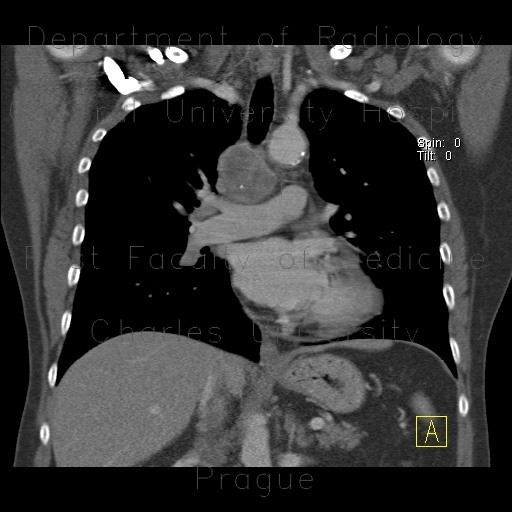

M/21

Incidental detected mass